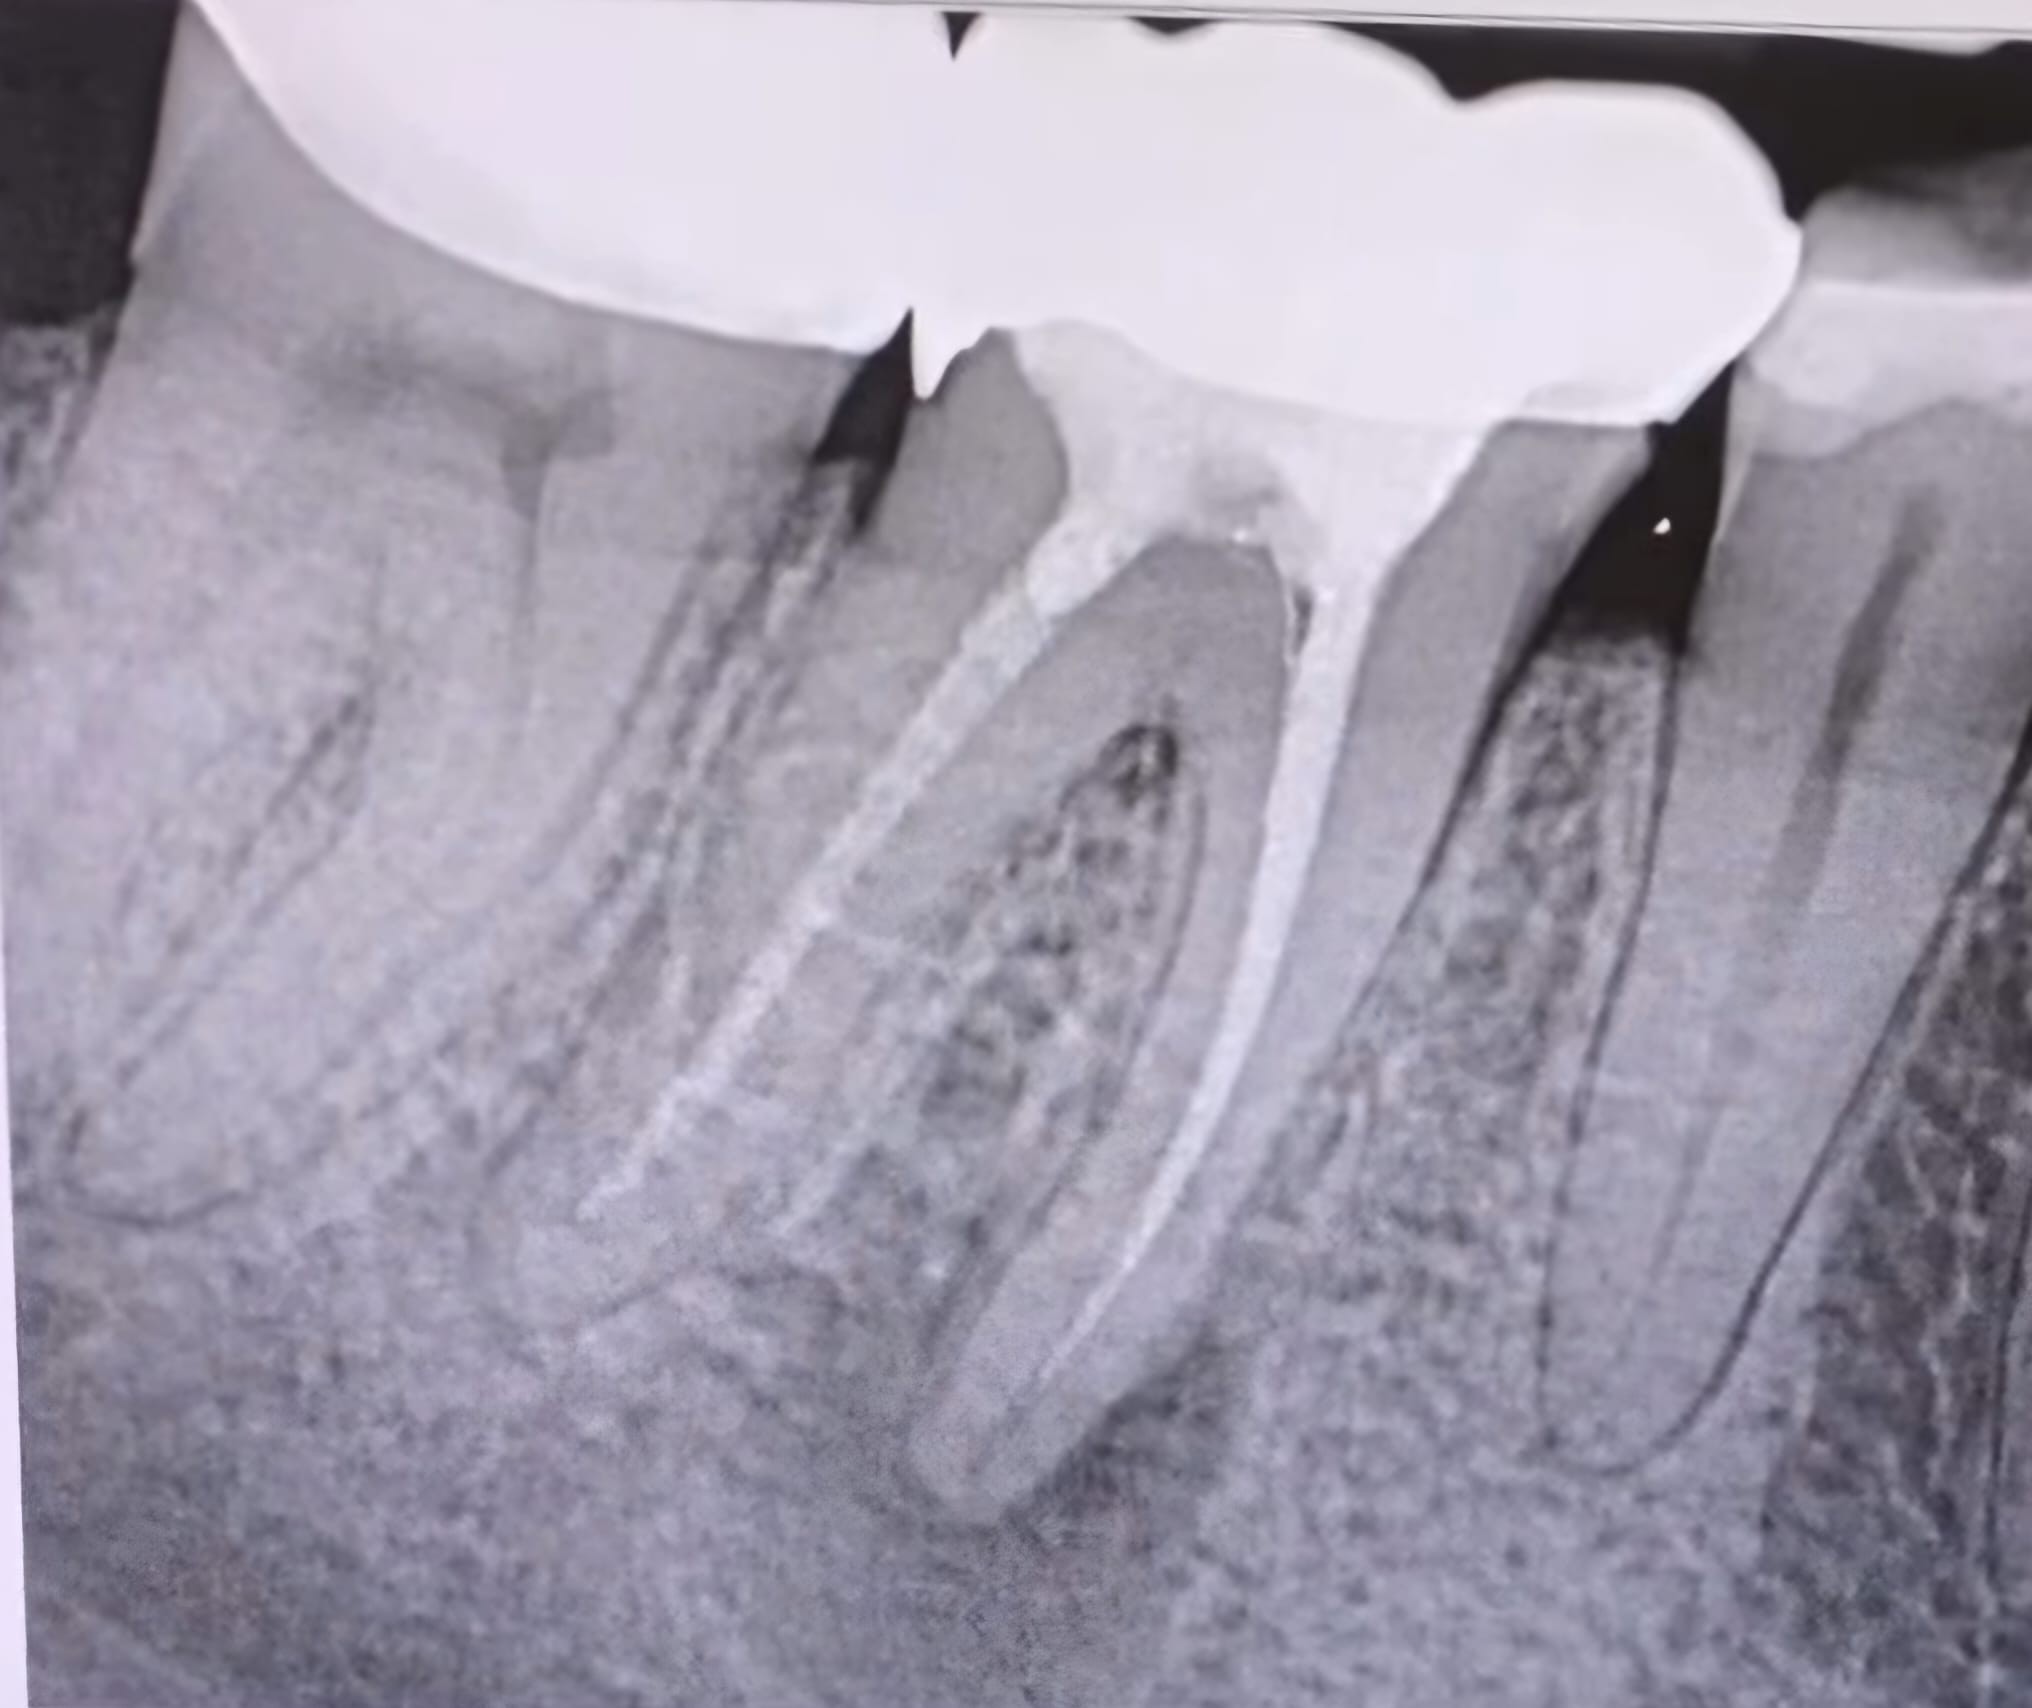

4. Evaluate the root canal treatment of tooth # 3.6?